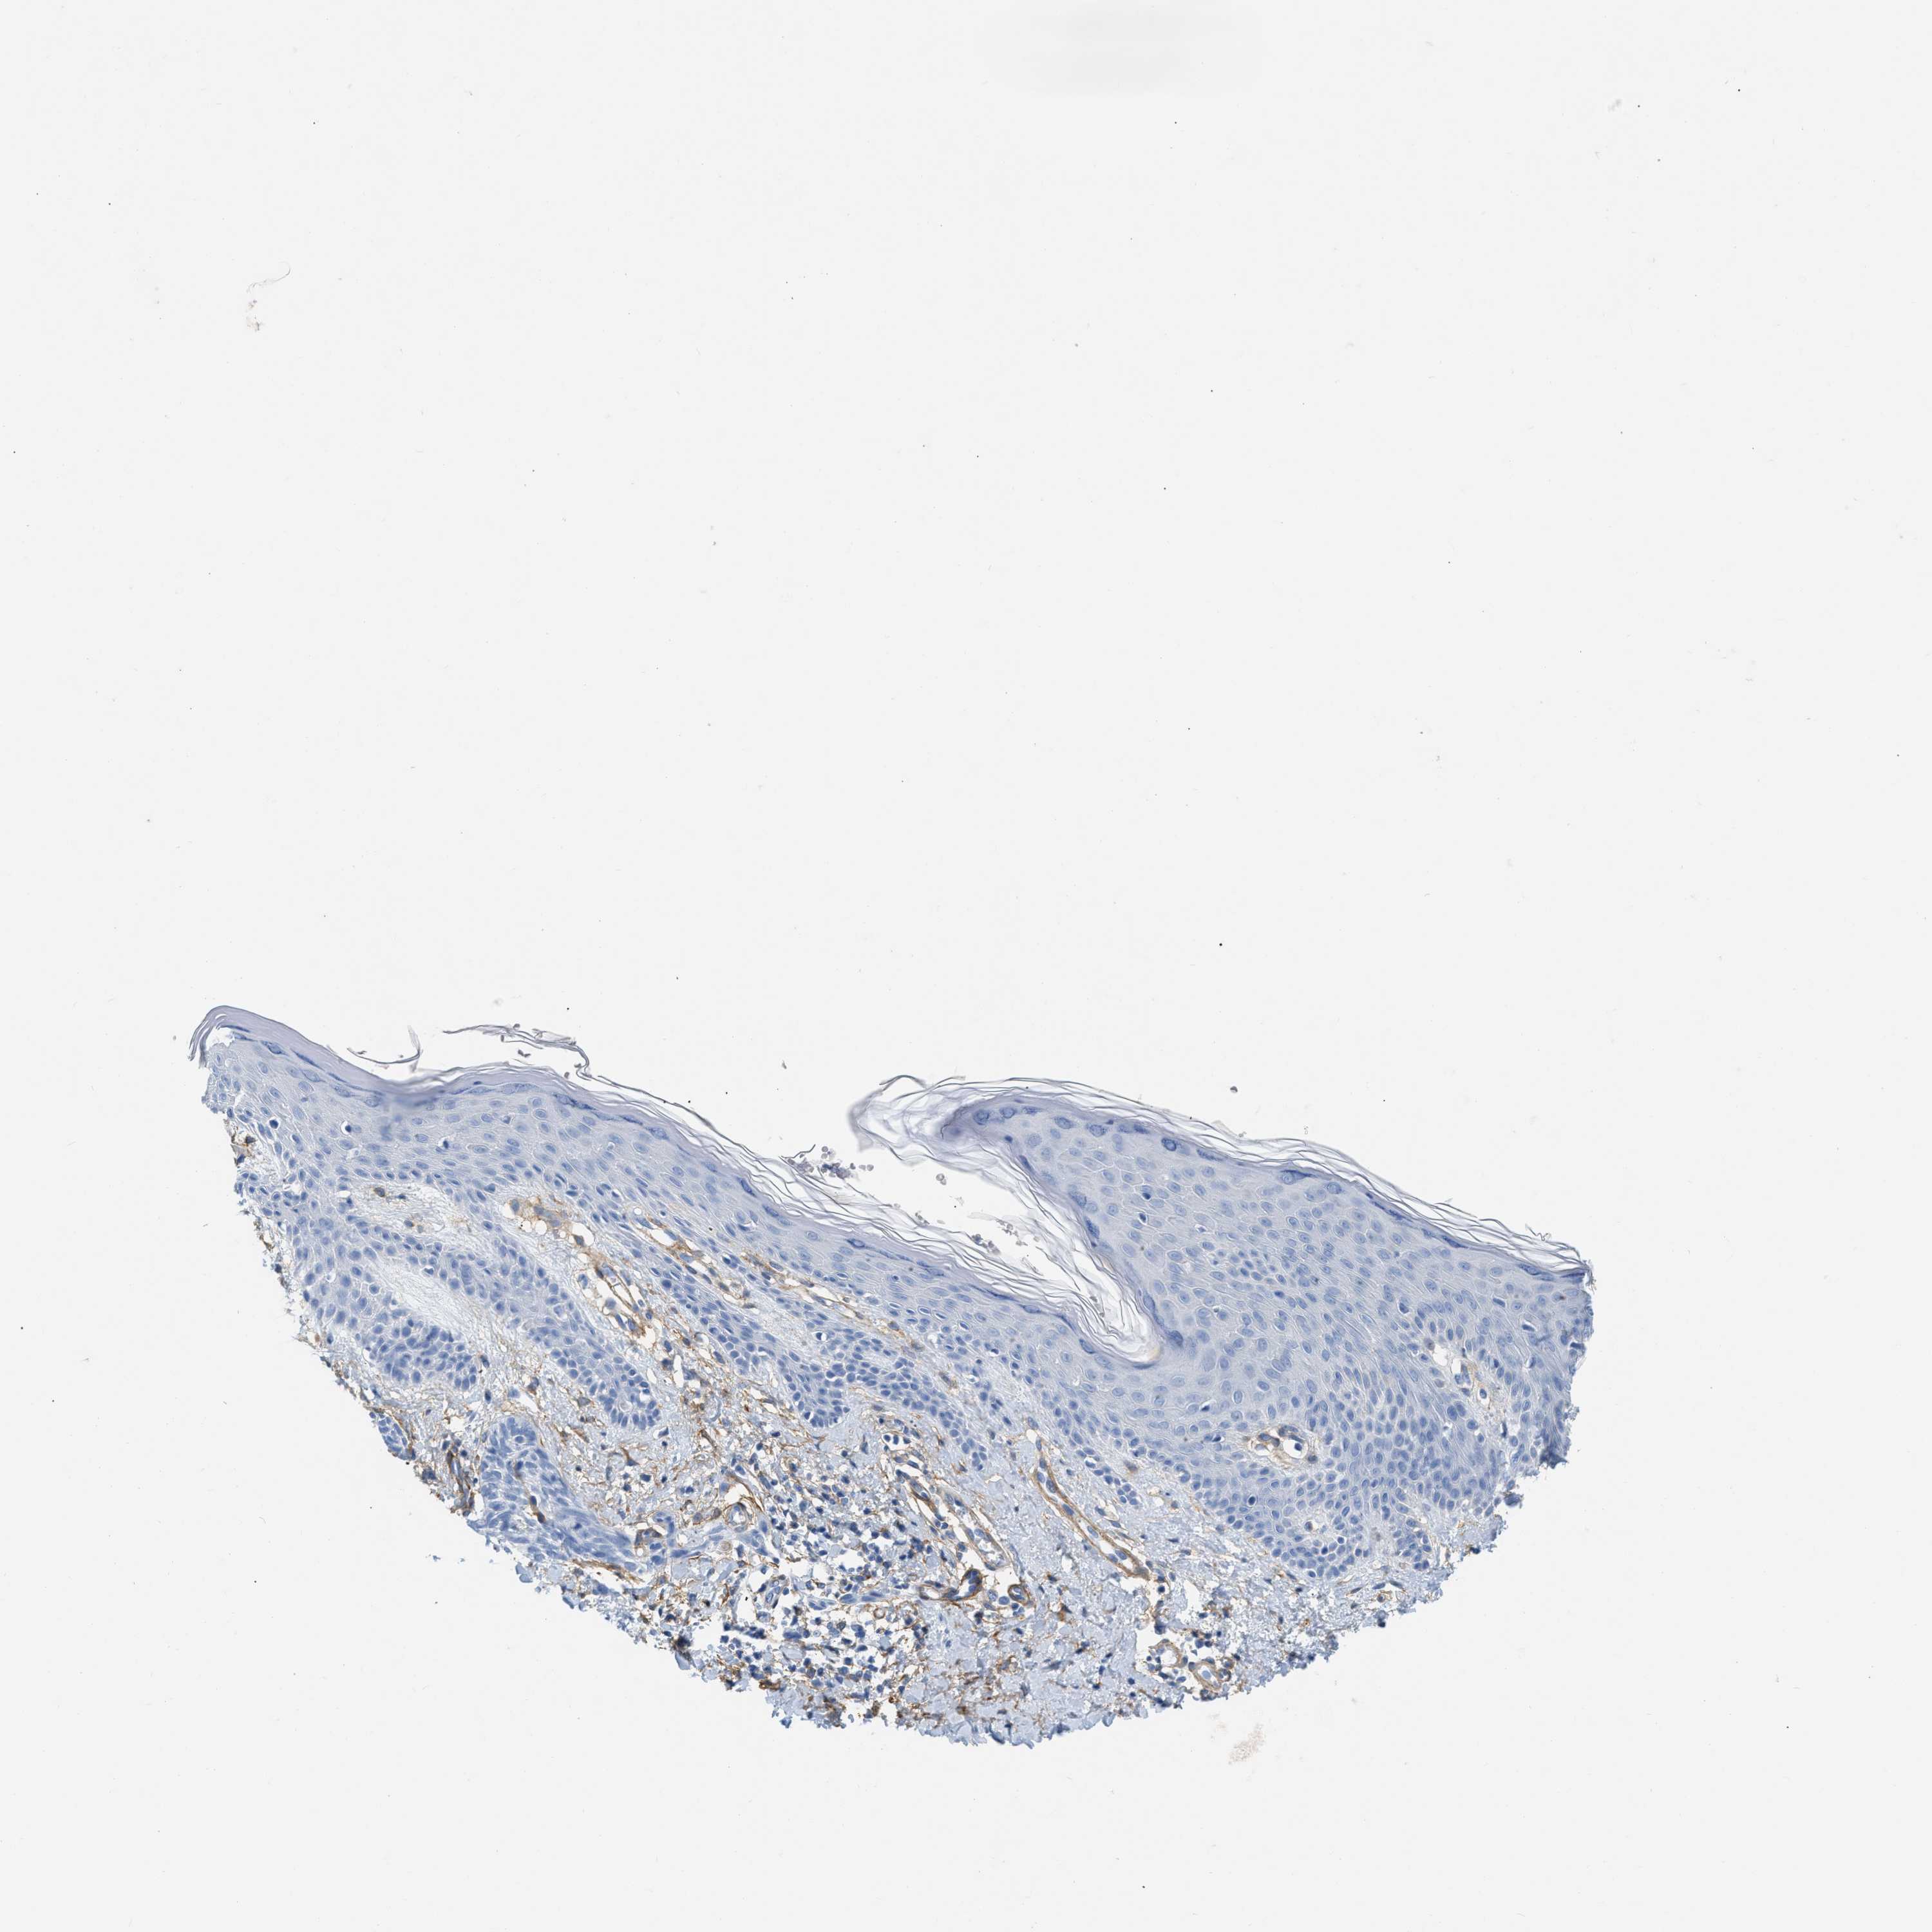

Basal cell and squamous cell cancer

SKIN CANCER - Protein expressioni

A mouse-over function shows sample information and annotation data. Click on an image to view it in a full screen mode. Samples can be filtered based on level of antibody staining by selecting one or several of the following categories: high, medium, low and not detected. The assay and annotation is described here.

Each image is clickable and will lead to virtual microscopy that enables deeper exploration of all samples and also displays staining intensity scores, fraction scores and subcellular localization as well as patient and tissue information for each sample.

Antibody CAB003842

Squamous cell carcinoma, NOS

Basal cell carcinoma

Squamous cell carcinoma in situ, NOS

Squamous cell carcinoma, metastatic, NOS